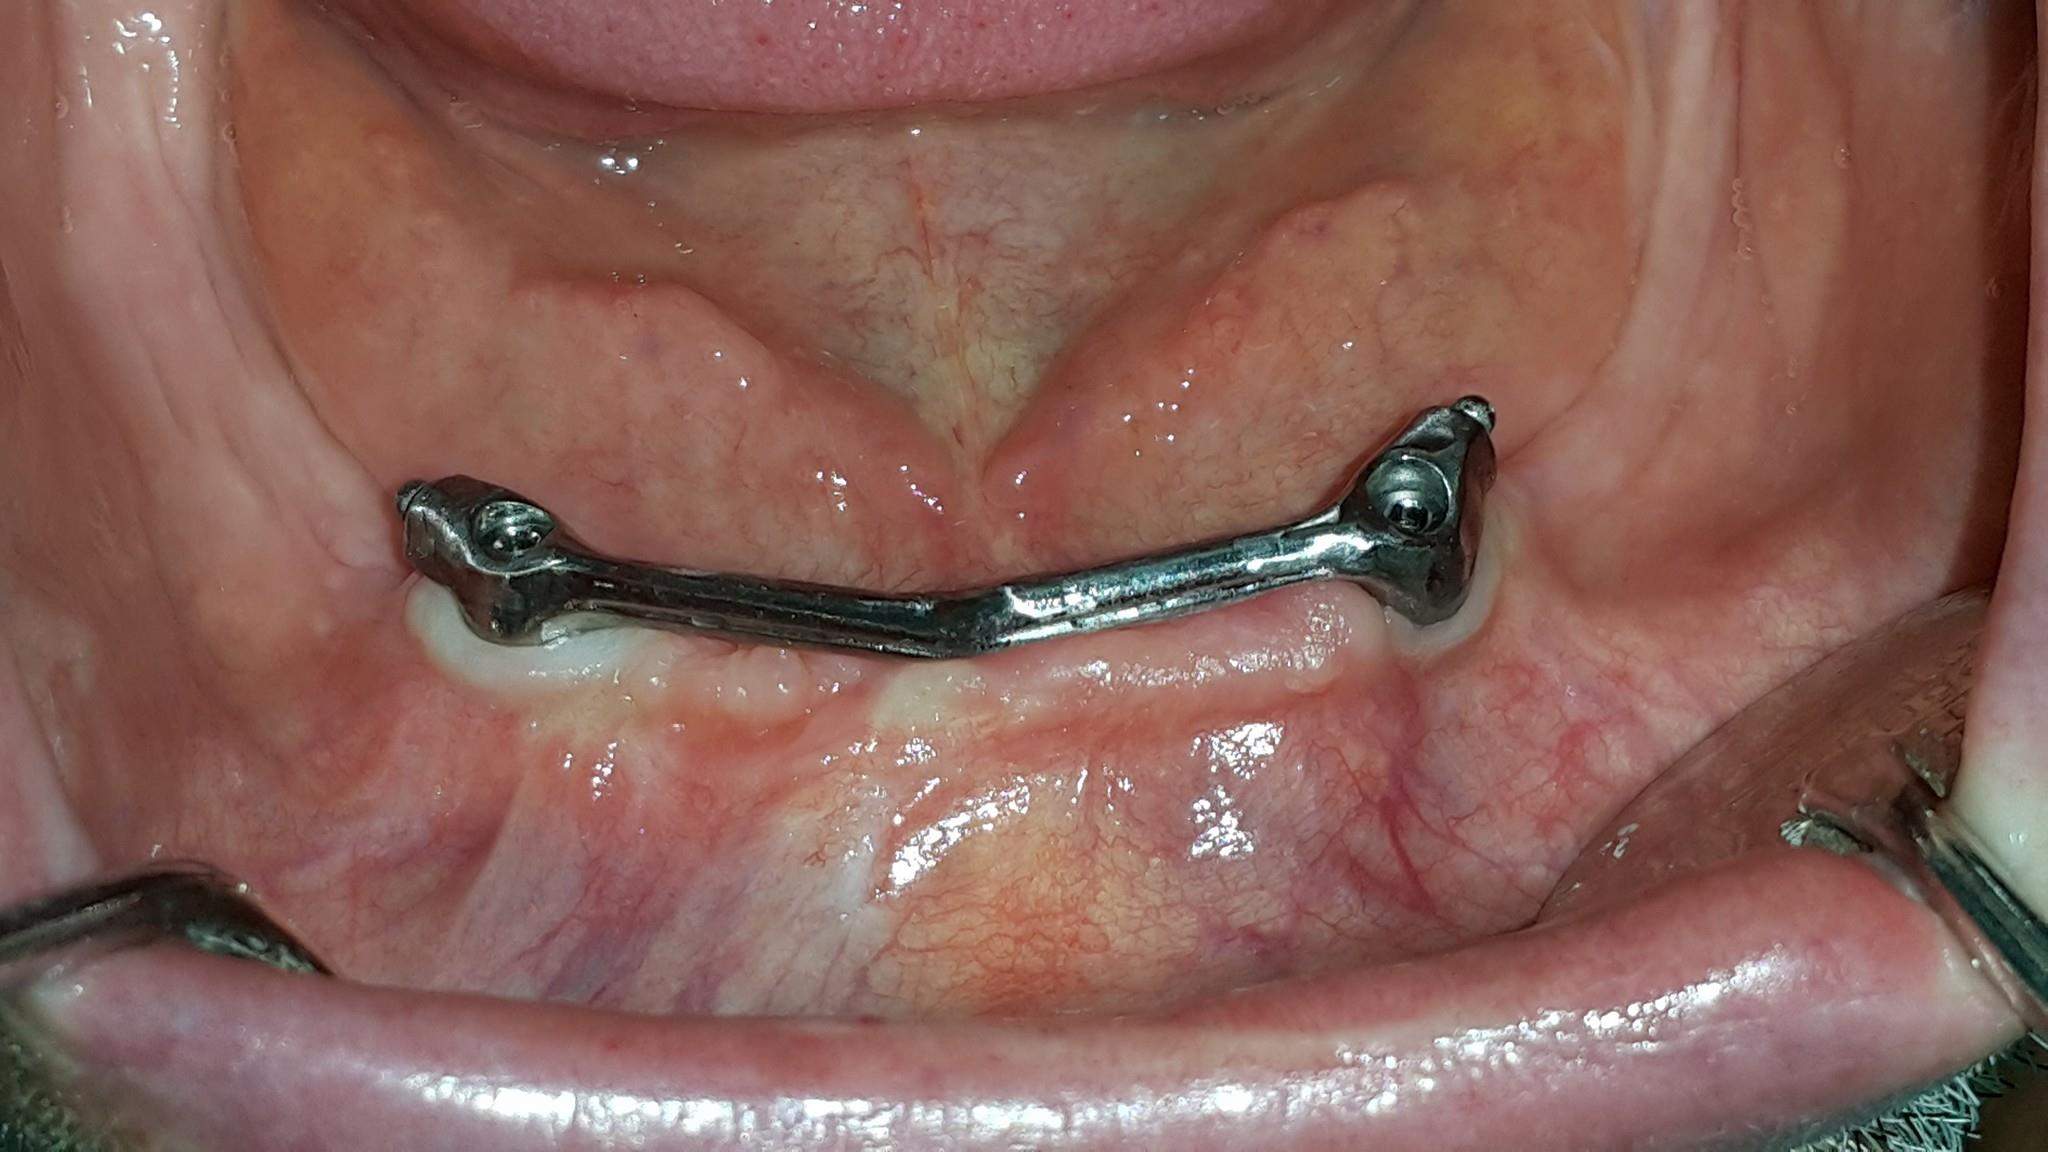

Uslijed potpune atrofije donjeg alveolarnog grebena pacijent nikako nije mogao nositi donju totalnu protezu, te mu je predložena ugradnja dentalnih implantata, i izrada Dolderove prečke preko koje se proteza snažno pričvršćuje.